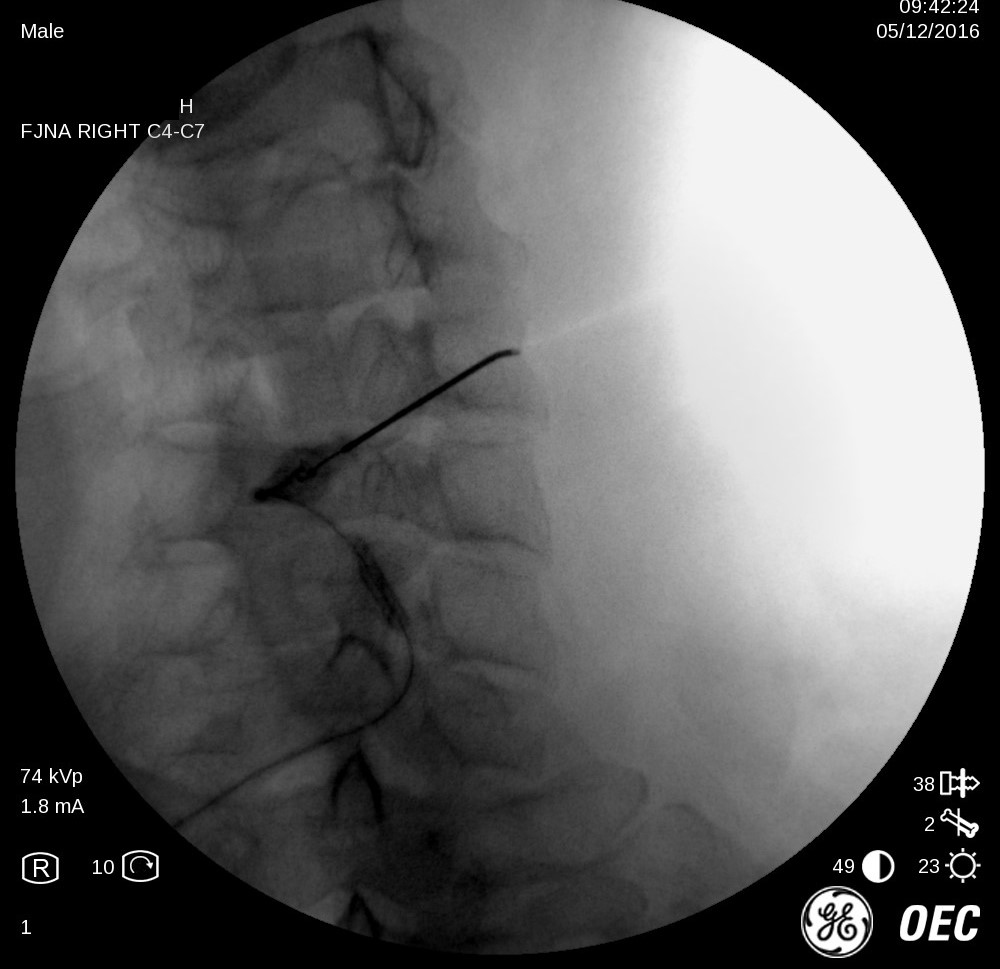

cervical-facets-US-Ahmed-Zaghlol